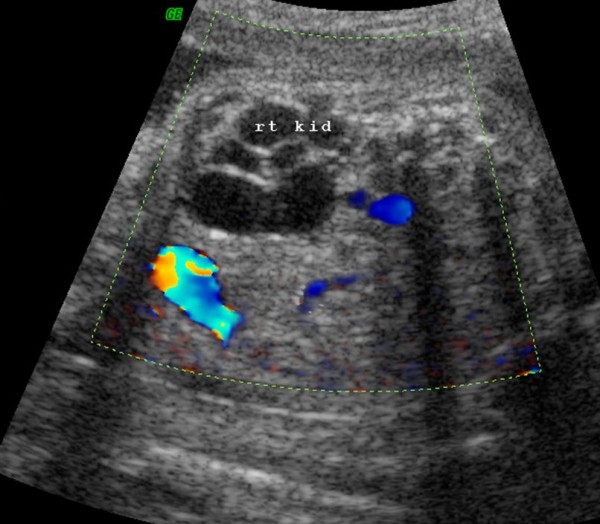

Last night around 7:45PM I found out I was pregnant, and at the same found out I had a miscarriage. I'm 17 years old, and i never intended to have have sex EVER, but I did. I never intended to get pregnant, but i did. I had a purity ring and I dedicated my life to Christ. I never wanted anything to happen like this. At least not this way. I wanted to wait till marriage, and proudly have a baby. I have ALWAYS wanted to be a mother so badly, and be a housewife. That was my dream and it still is. I have lost something dear and special to me and I can't bring it back. I don't even know if it was a boy or a girl. If it was a girl, well I have to have about a thousand kids. I have so many names for girls that I love. The same thing goes for boys, if I had one. I mean I had a lot of miscarriage symptoms, the over amount of bleeding in the first trimester, the intense cramps that they make you fall over in tears or you loss your breath from, grayish (fetal) tissue coming from the vagina. Plus I drink a lot of caffine, that not big of a risk, but it is still a risk. My family has always had problems with pregnancy and birthing a children. I took an ultra sound and it showed me what the fetus looked like. If I would have never had sex this would have never happened. I wish I could have done something to have that fetus still alive and in me cause it would be mine and I would love it forever. But I will always be sorry that I lost it, because It was my fault. I hope it never happens again when i am married because it is making me fall to bits.